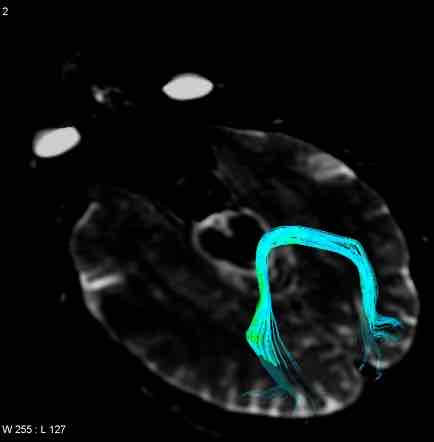

co tworzy kleszcze

skraje włókna promienistości ciała modzelowatego

jakie są kleszcze

kleszcze mniejsze / czołowe (forceps minor / frontalis)

kleszcze większe / potyliczne (forceps major / occipitalis)

kleszcze potyliczne / większe (forceps major / occipitalis)

włókna spodiła wielkiego łączące ze sobą najdalej ku tyłowie wysunięte punkty biegunów potylicznych

włókna spodiła wielkiego łączące ze sobą najdalej do przodu wysunięte punkty obu biegunów czołowych